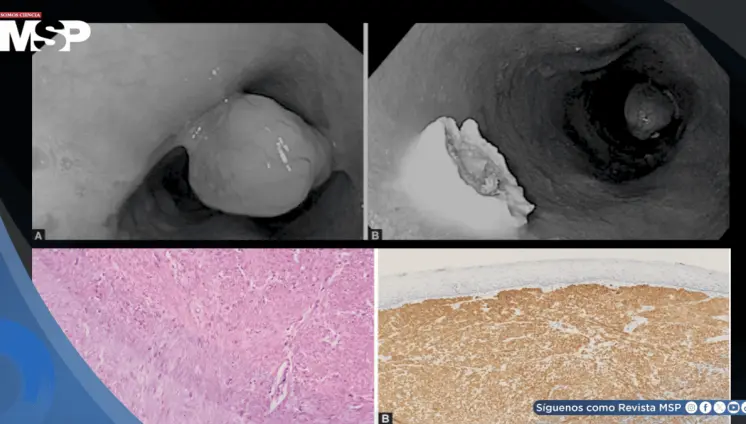

Cáncer renal reaparece como metástasis pancreática siete años después en mujer de 60 años con hematuria

Panel Educativo: Claves clínicas en el abordaje de cáncer gástrico